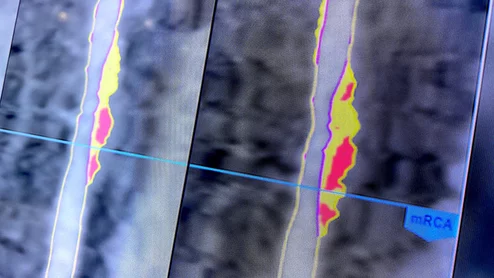

Herbert D. Aronow, MD, MPH, FACC, FSCAI, FSVM, medical director, heart and vascular service line and the Benson Ford Chair in Cardiology at Henry Ford Health, member of board, Society for Cardiovascular Angiography and Interventions (SCAI), the explains how hospitals can set up renal denervation (RDN) programs and how the reimbursement landscape is changing with new Medicare coverage.

Herbert D. Aronow, MD, reviewed the many ways the reimbursement landscape is changing thanks to new Medicare policies. “This is a really exciting time in the renal denervation space," he said.